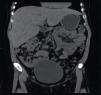

Mujer de 26 años de edad, con diagnóstico de diabetes mellitus tipo 1 (DM1) desde los 5 años. Descontrol crónico a pesar de múltiples esquemas de insulina con niveles de HbA1c 12%, conocida con retinopatía y neuropatía periférica. Cuadro clínico de un mes caracterizado por náuseas, vómitos y dolor abdominal. A la exploración presentó talla inferior a la esperada, sobrepeso, facies de aspecto cushingoide y hepatomegalia. Las pruebas de funcionamiento hepático solo mostraron aumento de transaminasas (ALT 158UI, AST 192UI) y FA 265UI. Se descartó etiología viral y autoinmune. Se realizó una TC simple de abdomen que reveló hepatomegalia de aspecto brillante (fig. 1).